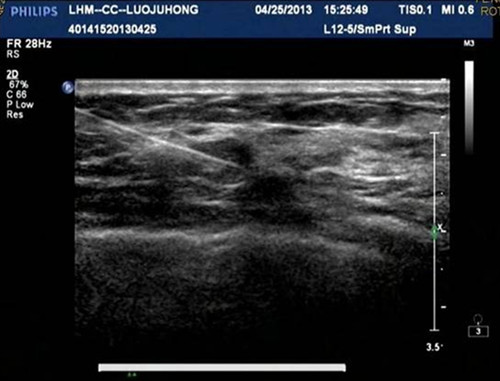

患者女性,43岁,因常规B超体检时左乳房发现一小结节,触诊不清。经高频彩超扫描后,发现有大小约5*6mm的小结节,根据乳腺影像报告和数据系统(BI-RADS)为4类。由于结节小、手诊未能触及,给外科手术切除带来一定的困难。为能更好的满足患者的健康和心理要求,更加精准定位结节,引导手术医师能完整切除肿物而保留正常乳腺组织,超声科主任刘红敏与患者充分沟通后,决定为其实施高频彩超引导下置入乳腺定位针定位联合体表标志切除小结节。功夫不负有心人,手术用时30分钟,成功为患者切除了大小为5*6mm的小结节,经病理化验后确诊为乳腺腺癌。

近年来,乳腺癌是危害女性健康的第一位恶性肿瘤,乳腺癌的早期发现、早期诊断、早期治疗是提高乳腺癌生存率和降低死亡率的决定性因素, 而早期明确诊断具有最重要的临床意义,尤其当病灶尚不能被触及时就被发现,可以大大改善预后,甚至大部分可以达到根治水平。因高频超声图像分辨高,能清晰显示乳腺结节,内蕊钢丝前端有Y型倒钩的乳腺定位针定位准确,可实时显示进针途径、方向及针尖与病变的位置关系,在操作中可及时调整进针角度和方向,使针尖准确到达结节内,并将带有倒钩的导丝留置于瘤体内,不易脱出,定位准确率高。为了更精确引导术者完整切除肿物而保留正常乳腺组织,常联合在超声显示下用记号笔在皮肤表面勾画出乳腺病灶范围,进行体表标记(双定位)。此操作简单方便、安全、无放射、并发症少,可以指导手术医生选择适当的手术切口位置和行径,对不能触及的乳腺小结节实行准确无误的切除活检,组织损伤小,取材精确,病理结果可靠,为乳腺小结节的早期定性诊断提供了可靠途径,也提高了早期隐匿性乳腺癌诊断的准确性,可把乳腺癌及其他乳腺病变消灭在萌芽之中,筑起健康乳腺的保护墙。